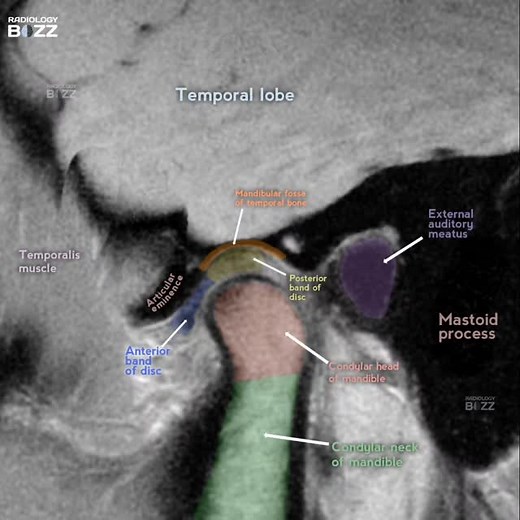

Anatomy - TMJ

Diagram - TMJ